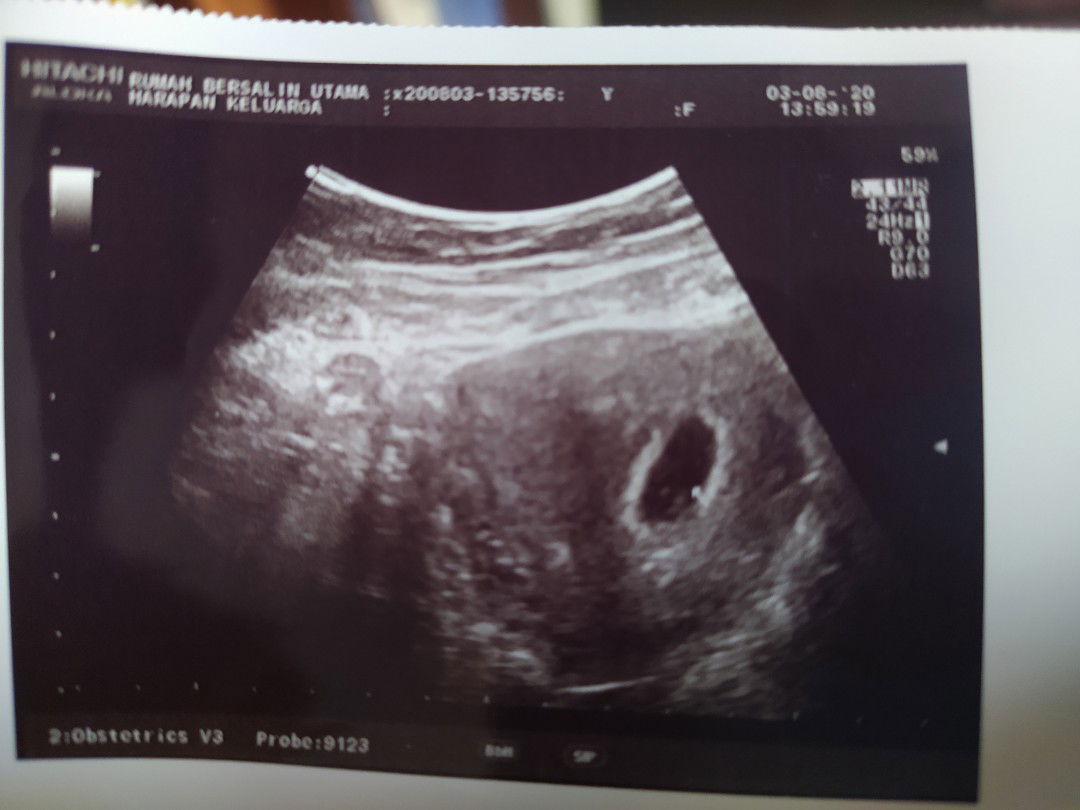

belum terlihat janin da djj

hamil 6minggu usg hanya terlihat kantongnya saja...apa normal ,,, Trauma karena pernah keguguran..